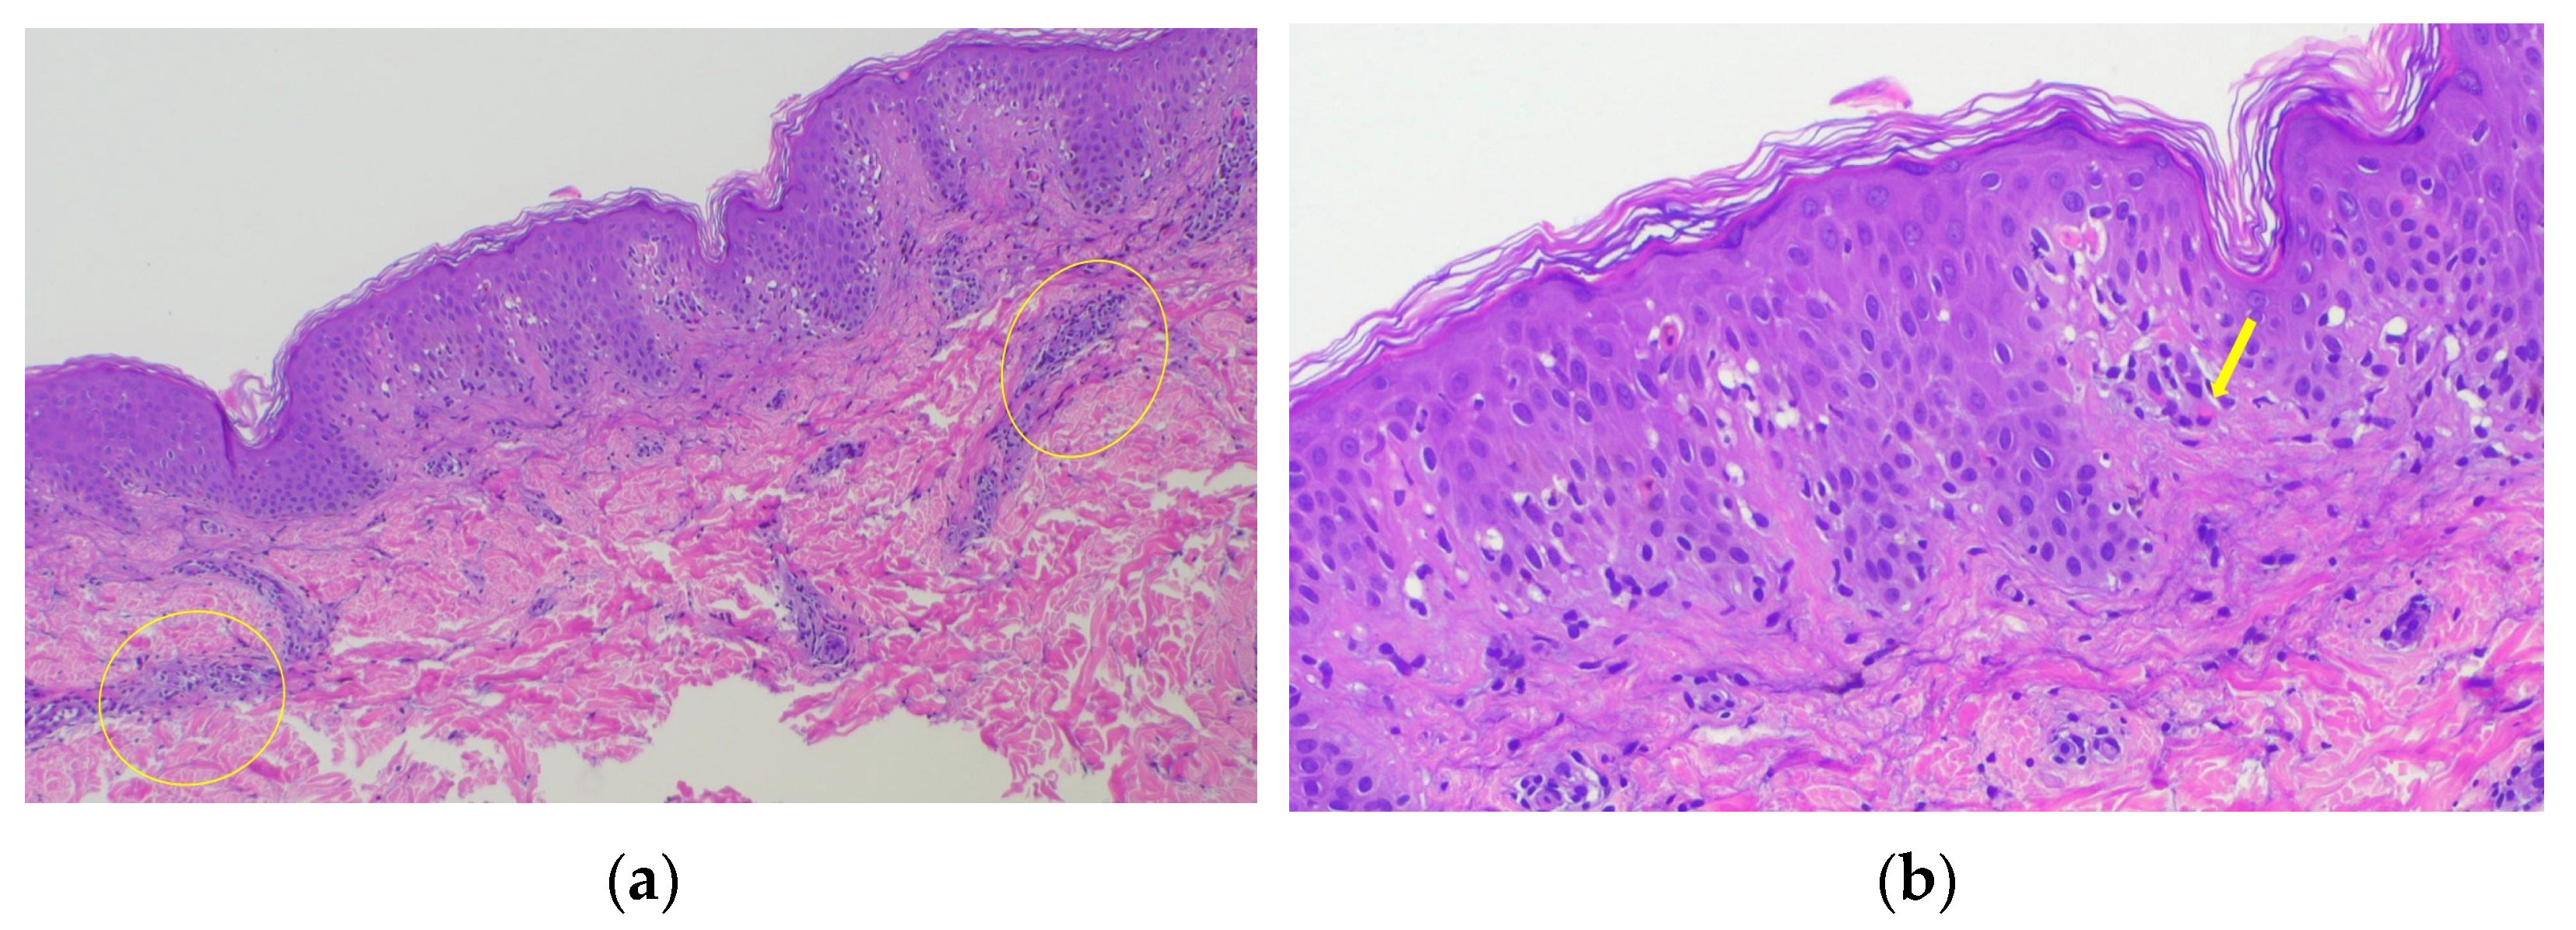

2. Case Presentation